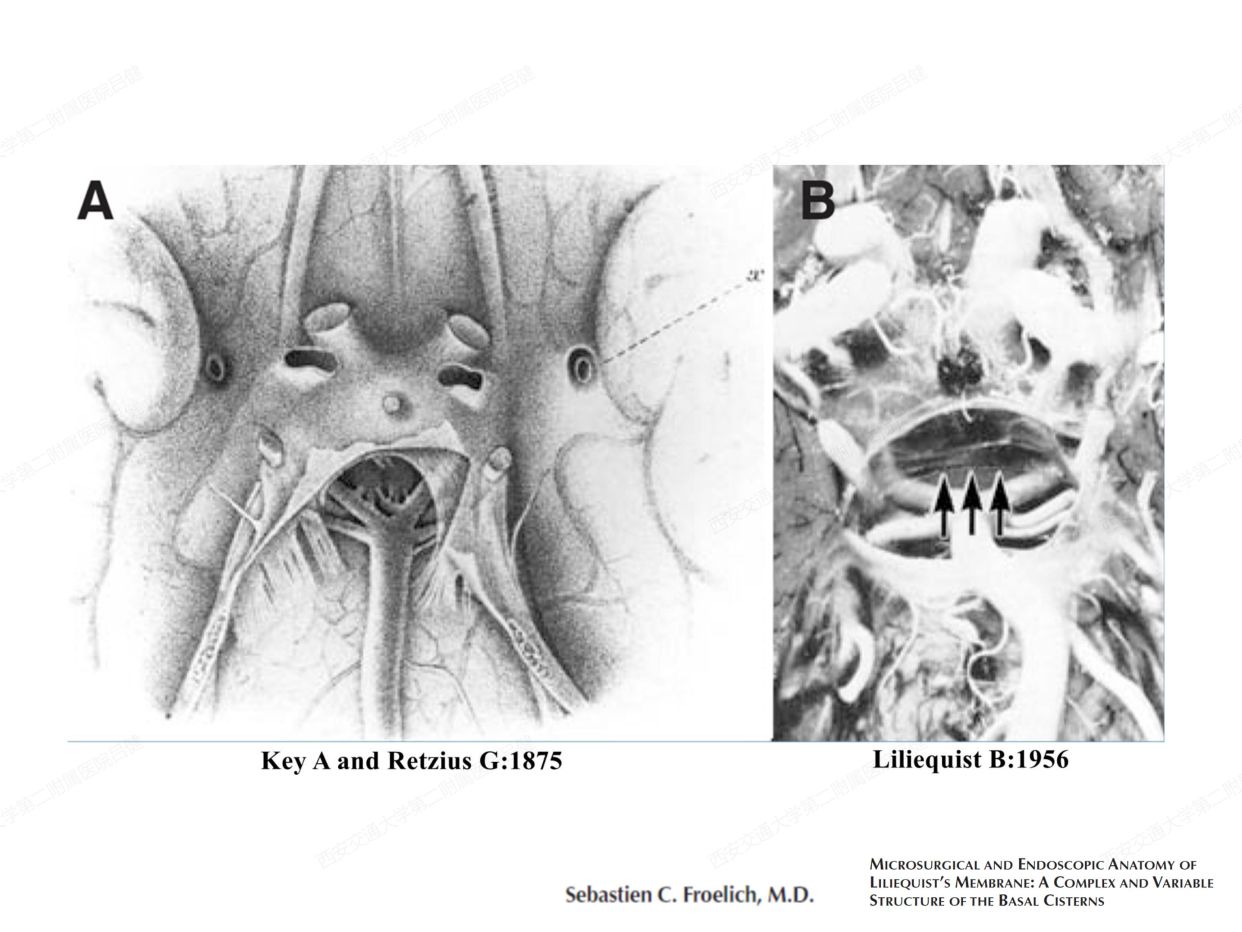

颅内蛛网膜和蛛网膜下池的解剖学研究意义

转自 神外前沿2020-6-22 解剖课件| 颅内蛛网膜和脑池的解剖研究-西交二院吕健